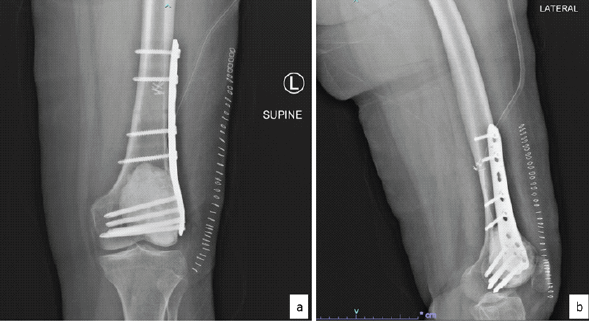

This was followed by biopsy of the lesion which revealed several fragments of cartilage with only a few fragments showing oval-to-spindle cell proliferation with areas of stromal hyalinization. No unequivocal substantial number of osteoclast-like giant cells was seen in the few tumor fragments. The tumor cells showed diffuse and strong nuclear positivity for H3.3G34W immunohistochemistry and only patchy weak nuclear positivity for SATB2 and were negative for CD99, CD34, STAT6, and S100. A diagnosis of GCT with unusual chondroid metaplasia was rendered (Fig. 3a, b, c, d, e). This case was discussed in the multidisciplinary meeting and it was decided to proceed with curettage with cementing and plating (Fig. 4) for this patient. Intraoperatively, frozen section was sent, which showed giant cells along with chondroid differentiation; this chondroid component was benign. Final histopathology revealed similar findings along with areas with characteristic histopathological findings of GCT of bone in the form of proliferation of mononuclear stromal cells and evenly dispersed numerous osteoclast-like giant cells. Mitosis was infrequent, and no atypical mitotic figure was noted. No area of necrosis was identified. The cartilaginous component was composed of well-differentiated hyaline cartilage with basophilic matrix. There was no increase in cellularity or nuclear atypia. The immunohistochemistry for H3.3G34W was diffusely and strongly positive in the stromal component of the tumor, whereas it was negative in the osteoclast-like giant cells and the cartilage matrix (Fig. 3f, g, h). The patient was kept under observation. This patient has been on follow-up 18-month post-surgery and is doing fine without any symptoms, with a knee range of motion from 0 to 110°.

Figure 4: Post-operative X-rays. (a) Anteroposterior and (b) lateral view.